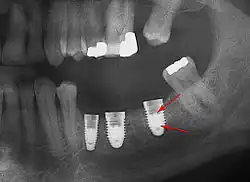

Для разрушения абатментных винтов (стрелка) в 3 имплантатах необходимо снять оставшуюся часть винта и заменить его.